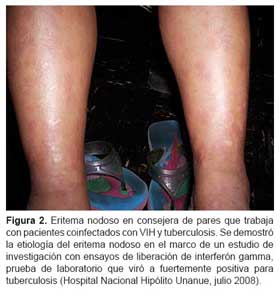

Tuberculosis: diversas manifestaciones de una misma enfermedad

Tradicionalmente se ha definido a la sífilis como la gran simuladora de las enfermedades infectocontagiosas, sin embargo la tuberculosis es igual de proteiforme en cuanto a sus manifestaciones clínicas. Esto se debe, entre otras causas, a tres factores importantes.

En segundo lugar, al tratarse de una infección intracelular, genera una respuesta inmune en la que prima ocasionalmente la liberación de citoquinas pro-inflamatorias, desencadenando procesos que pueden simular fenómenos autoinmunes. Y por último, su asociación con comorbilidades significativas que pueden ser tanto condicionantes de tuberculosis como condicionadas por la misma y que tienen su propia riqueza semiológica.

Estas manifestaciones atípicas de tuberculosis, tan variables, deben generar sospecha en el personal de salud, siendo una enfermedad muy prevalente en nuestro medio. Debemos recordar que ante un cuadro clínico raro, es más probable la manifestación atípica de una enfermedad frecuente que la manifestación típica de una enfermedad infrecuente.